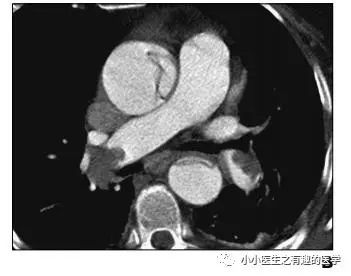

如图,高密度影的那一条。

不怕,有增强CT证实。

是不是很有趣。